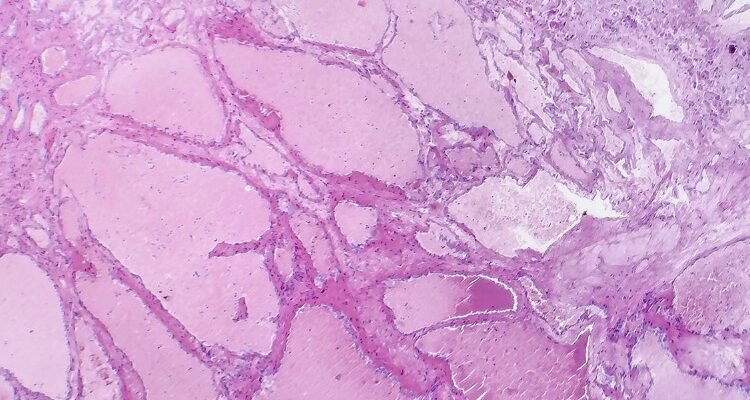

- Кавернозна гемангіома: Пухлина з порожнинами, заповненими кров’ю.